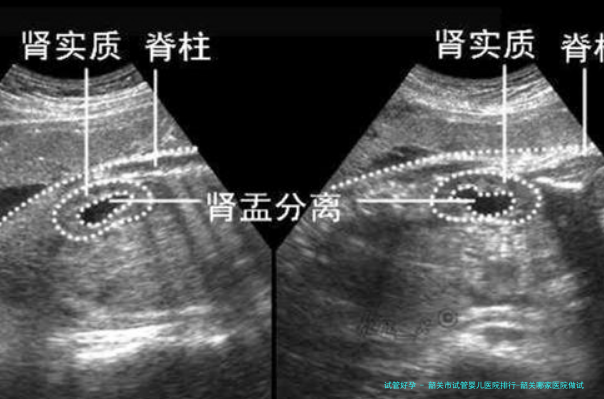

促排卵期间需定时监测卵泡发育情况。